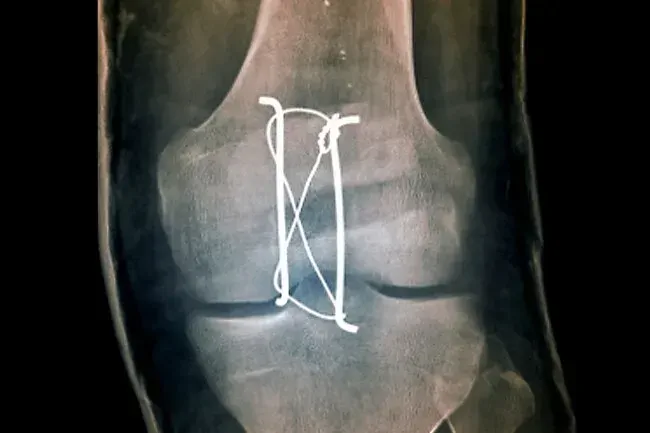

Patella Fraktur

Sie können die Knochen in Ihrem Knie knacken oder brechen, aber die Kniescheibe oder Patella ist am häufigsten. Verletzungen hier resultieren normalerweise aus einem plötzlichen Sturz oder einem Autounfall. Sie haben Schmerzen und Schwellungen am Knie und Sie können Ihr Bein möglicherweise nicht glätten oder gar gehen. Die Kniescheibe bricht leichter aus, wenn Sie altern, besonders wenn Sie spröde Knochen haben (Osteoporose).

Patella Fraktur Repair

Die Behandlung hängt von der Art der Unterbrechung ab. Wenn die Teile nahe beieinander liegen und sich wie ein Puzzle -Puzzle aufstellen, benötigen Sie möglicherweise nur eine Schiene, mit der sie wieder zusammenwachsen können. Aber wenn es viele Knochenstücke gibt oder dass sie zu weit voneinander entfernt sind, kann Ihr Arzt eine Operation vorschlagen. Möglicherweise müssen sie Schrauben und Teller verwenden, um sie wieder zusammenzusetzen.